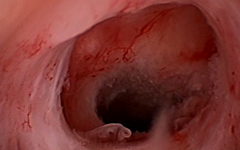

子宮憩室是一種常見(jiàn)的婦科疾病,是指在子宮肌層內(nèi)出現(xiàn)的小囊腫。雖然它聽(tīng)起來(lái)有些嚇人,但實(shí)際上大多數(shù)子宮憩室是良性的,并不會(huì)影響日常生活。許多女性在生育過(guò)程中可能發(fā)...